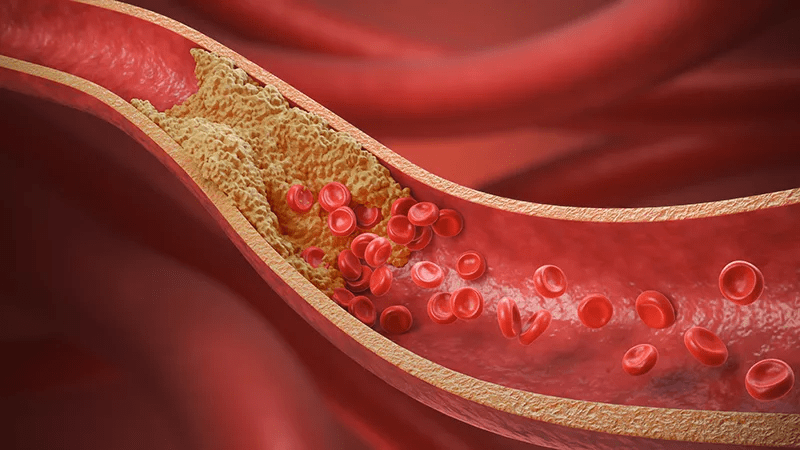

Artery blockages don’t appear overnight. They build slowly, quietly, and often without pain. That’s why many adults go years without realizing their arteries may be narrowing. The danger comes when cholesterol, inflammation, or plaque reduces blood flow.

You might feel normal most days. Maybe a little slower. Maybe a little more tired. But nothing that screams “heart trouble.” That’s exactly why many people ignore the early signs—until symptoms suddenly get harder to dismiss.